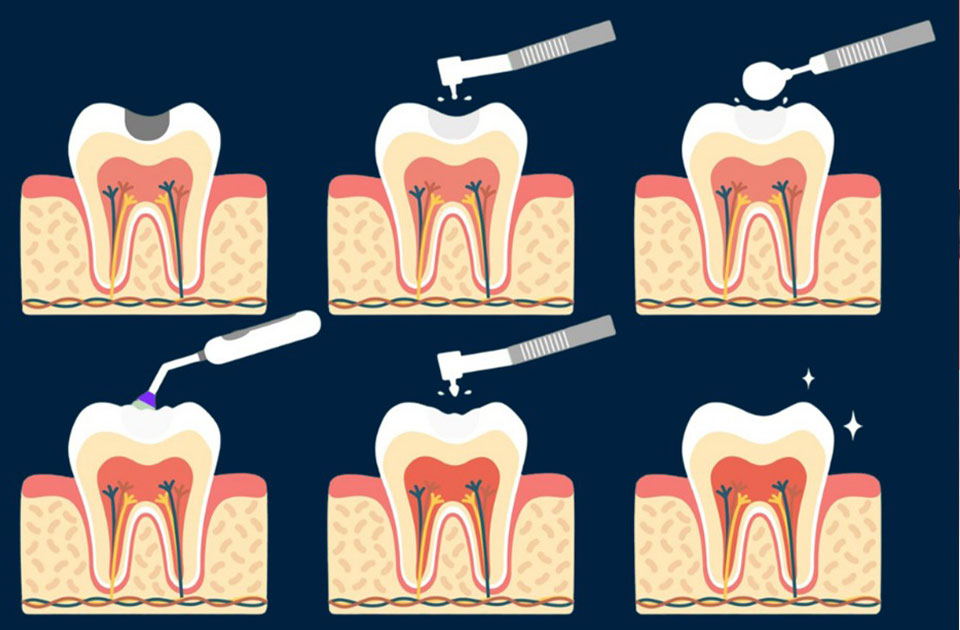

برای ترمیم دندان یا همان پر کردن دندان از انواع مختلفی از مواد پر کننده استفاده می شود . نوع مواد پز کننده مورد استفاده بستگی به شرایط پوسیدگی و عوامل دیگری مانند حساسیت یک فرد به آن ماده دارد . دقت کنید که هزینه پر کردن دندان با هر ماده متفاوت است .

انواع مختلف موادی که برای ترمیم دندان بکار برده می شود عبارتند از :